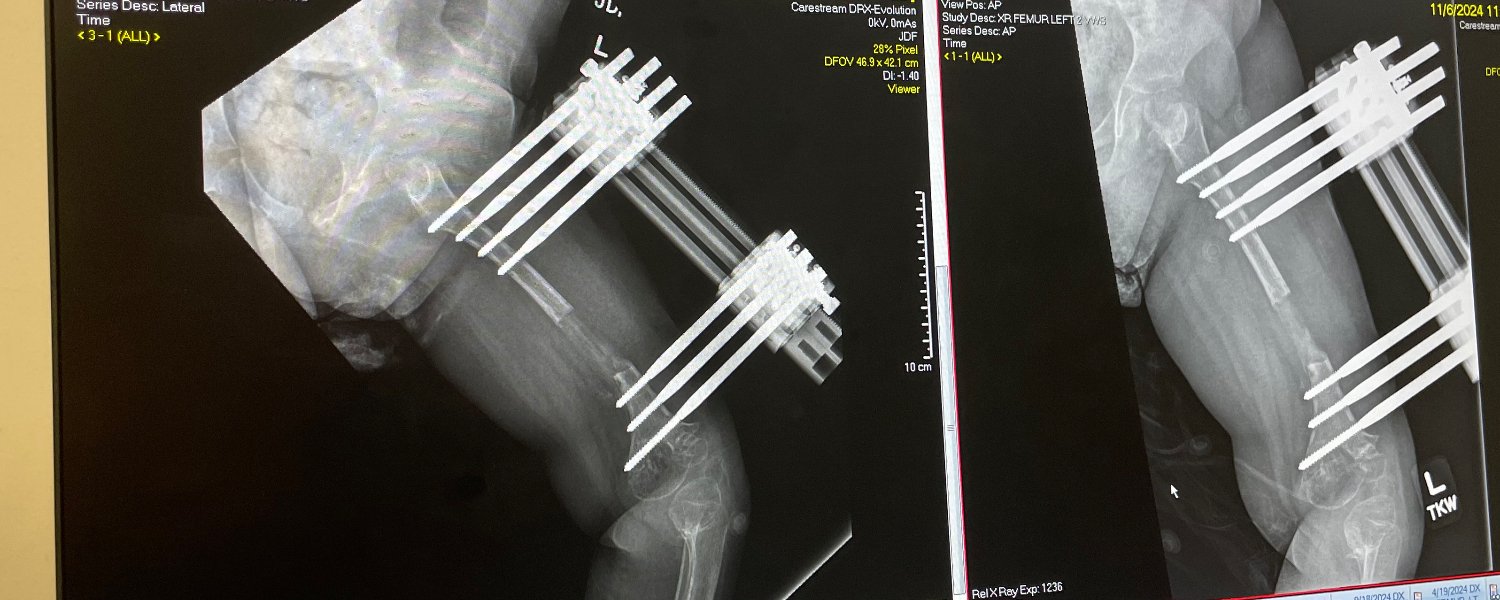

River, her twin sister, August, and family have been extended guests at the Ronald McDonald House Charities of Maryland on and off since 2024. Our family will be returning for an extended stay this Spring while River receives further orthopedic treatments at Johns Hopkins Hospital. After undergoing more than five surgeries, you would think that River would not want to return to Baltimore, but because of RMHC, she and her sister count down the 'sleeps' until River's next appointments. Having spent well over 200 days at the House, our family can absolutely attest to the miracles that RMHC Maryland provides for families.